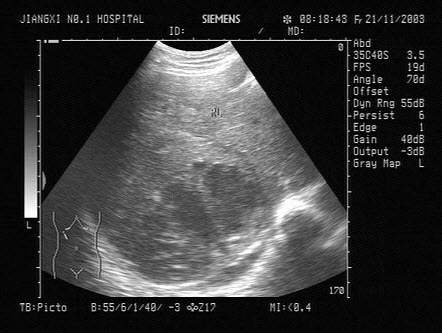

30、单项选择题

一患者,发热,右上腹痛,血常规检查白细胞增多。结合超声声像图,诊断为()

A.肝脓肿

B.肝血管瘤

C.肝癌

D.脂肪肝

E.肝囊肿